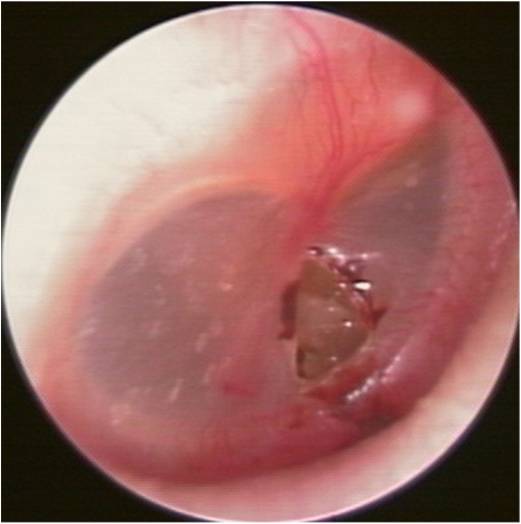

・外力により鼓膜に大きな力がかかり、鼓膜に穴が開いてしまった状態です。

・穿孔が小さいものでは数週間で自然に閉じる場合もありますが、それまで正常であった耳が突然に難聴になるので、患者さんはたいそう不便を感じます。

・そのため、当科ではなるべく早く応急処置を行い、人工鼓膜で穴をふさぎます。

・90%は外来での保存的な治療で1ヶ月以内に穿孔が閉鎖しますが、穴が大きなもの、もともと鼓膜が薄いもの、感染を起こして中耳炎を併発したものでは穴が閉じません。

・その場合は鼓膜形成術(接着法)と言って、外耳道経由で自分の皮下組織を鼓膜穿孔部に自家移植して穴をふさぐ手術をします。日帰りまたは1泊の手術で対応が可能です。